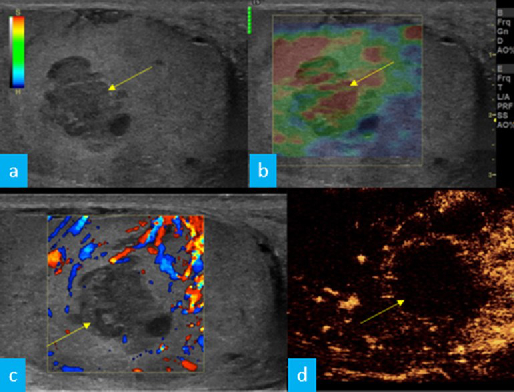

Imaging and Targeted Biopsy of the Genitourinary (GU) Tract

Friedrich Aigner

- Multiparametric ultrasound of the scrotum

- Multiparametric ultrasound of the prostate

- Multiparametric MRI of the prostate

- Fusion imaging of the GU-tract

- Fusion targeted biopsy of the prostate

The simultaneous application of structural and functional imaging techniques is described as multiparametric (MP) (Fig. 9). Studies have shown that the MP approach results in greater diagnostic accuracy (Fig. 10).

The use of fusion imaging in uroradiology improves ultrasound lesion-detection rates, shows more reliable size controls at different time points, is an alternative to in-bore biopsies (Fig. 11) and can be used for focal therapy.